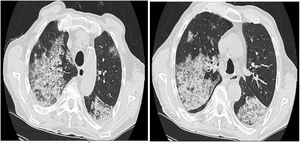

Tras notable cierto deterioro clínico durante los primeros días del ingreso, y ante la persistencia de hemoptisis franca objetivada y febrícula diaria, se solicitó tomografía computarizada (TC) de tórax para filiar el cuadro. Este mostraba áreas múltiples en vidrio deslustrado y patrón crazy paving, que podían ser compatibles con hemorragia alveolar, aunque no podía descartarse proceso neumónico multilobar. Se solicitaron determinaciones de autoinmunidad, baciloscopias y cultivos de esputo. Las determinaciones microbiológicas fueron negativas, y con la sospecha de que se tratara de una hemorragia alveolar de etiología autoinmune (aunque todavía pendientes de resultados de autoinmunidad) se decidió comenzar con bolos intravenosos de metilprednisolona, a dosis de 750mg/cada día/durante 3 días. Al segundo día del tratamiento con glucocorticoides recibimos los resultados que indicaban positividad para los anticuerpos anti-MBG. El paciente presentó aceptable tolerancia inicial a las dosis altas de glucocorticoides, con mejoría ostensible del estado general y cese de la expectoración hemoptoica.